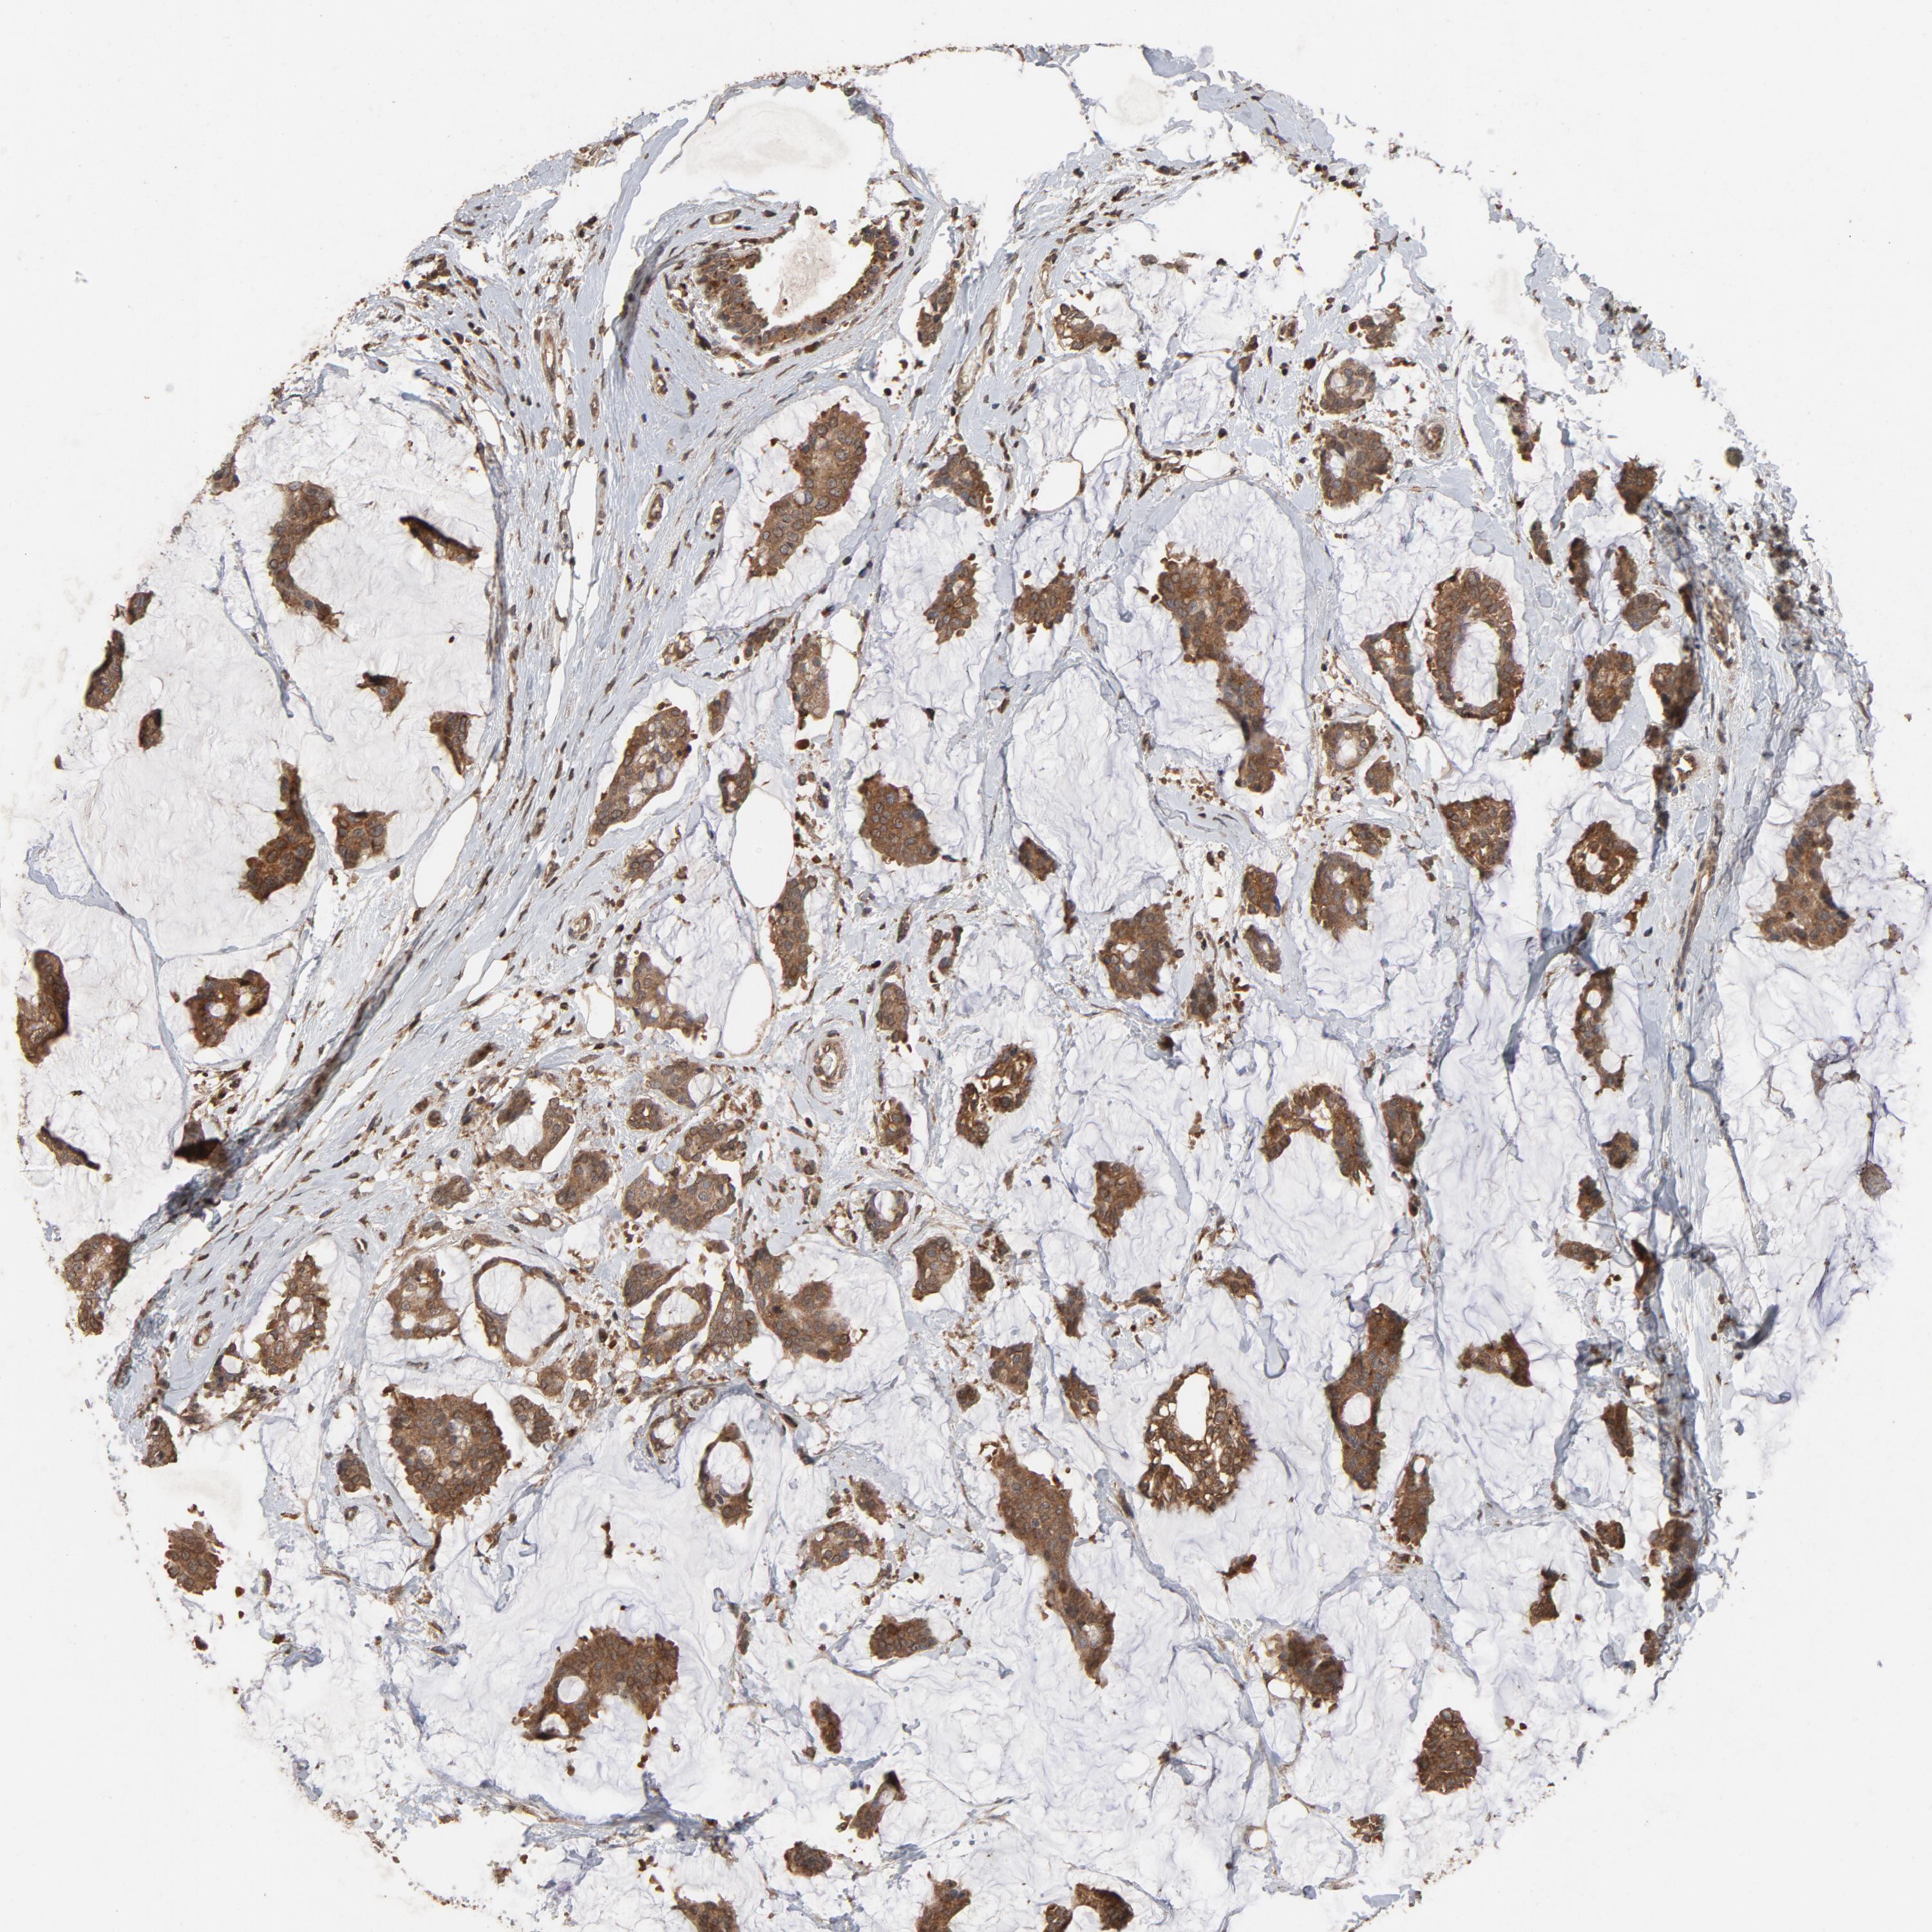

CANCER BREAST CANCER Show tissue menu

BRCA TCGA BRCA VALIDATION PROTEIN EXPRESSION

Breast cancer

Human cancer